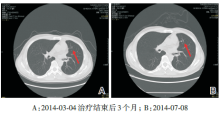

谢松喜:经科内讨论, 决定采用经皮肺穿刺活检+系统化疗+肺部手术+鼻咽部放疗的治疗方案。2013-08-01行经皮肺穿刺活检病理结果为肺浸润性腺癌。科室讨论此患者的诊断考虑为:鼻咽非角化型未分化癌伴双肺转移(cT3N1M1, Ⅳ C期), 左肺腺癌(cT1bN0M0, Ⅰ A期)。2013-08-16行第1周期TPF方案化疗(考虑本化疗方案同时对鼻咽癌及肺癌有效), 第2周期化疗后于2013-09-24复查胸部CT提示:与治疗前对比, 原发灶缩小, 转移灶减少、缩小(见图3)。治疗有效。予以继续完成共4周期TPF方案化疗。化疗结束后于2013-11-08行全胸腔镜下肺叶切除术+肺门纵隔淋巴结清扫术, 术后病理:(左下肺)肺浸润性腺癌, Ⅱ 级, 淋巴结可见癌转移(共1/9, 其中“ 段LN” 1/1)。术后恢复良好, 于2013-12-13开始行鼻咽+颈部调强放疗, 剂量66 Gy/30 F, 2014-01-23结束全程放疗。放疗后定期复查鼻咽MRI提示鼻咽肿瘤消失(见图4)。2014-07-08复查胸部CT示:左肺上叶前段结节较前增大, 考虑恶性可能性大。右肺两个小结节, 变化不大(见图5)。 此时, 我们需要明确:(1)诊断是否要改变?肺部小结节是良性或恶性?是肺多原发癌或鼻咽癌或肺癌转移?(2)左上肺新发增大的肺部结节如何处理?

图5 随访胸部CT新发病灶